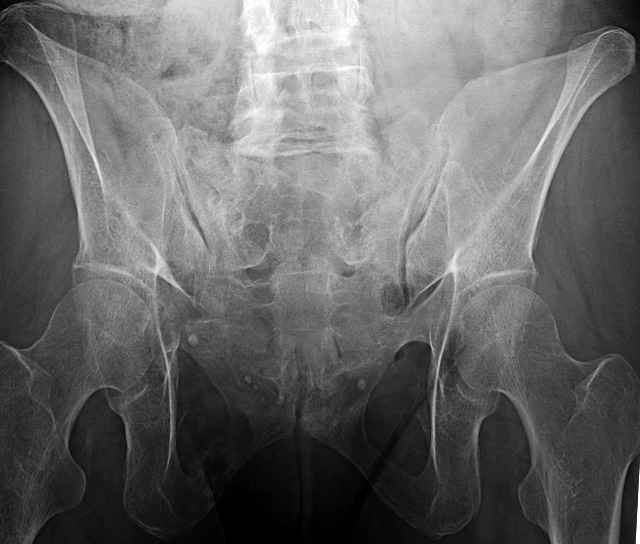

hello everyone, attached are images of a 59 yo female, admitted today after motor vehicle collision. Pt states her pelvis has been very painful ever since she fell on her buttocks from ground level a little over a year ago. medical history significant for scleroderma, raynauds syndrome, and COPD. no past surgeries.

pt states she is very limited in walking ability secondary to pain. she requires a cane or a walker. friends and family do her shopping. the pain is localized primarily around left upper groin. she points to the rami region.

I’ve operated on 30-35 similar symptomatic patients... usually females in that same age range and most with prior trauma and then with sustained chronic activity related pain due to presumed insufficient healing and resultant ring instability (enough to hurt but not displace too much)...almost all have xray evidence of most of us would consider “hypertrophic” ramus nonunions, and most all have some form of sacral or other posterior ring corresponding injury.

If you examine them for mechanical ring instability, you’ll feel them collapse in your hands as you do... most are overweight to fat to downright obese so the mechanical examination can be a real challenge, but when you anesthetize them you can repeat it under fluoroscopy and see the ramus collapse and displace.

54 yo Female Fell c/o Pain

Initial Films

?Instability on Exam - Limited by Pain

NonOp Initial Mgmt